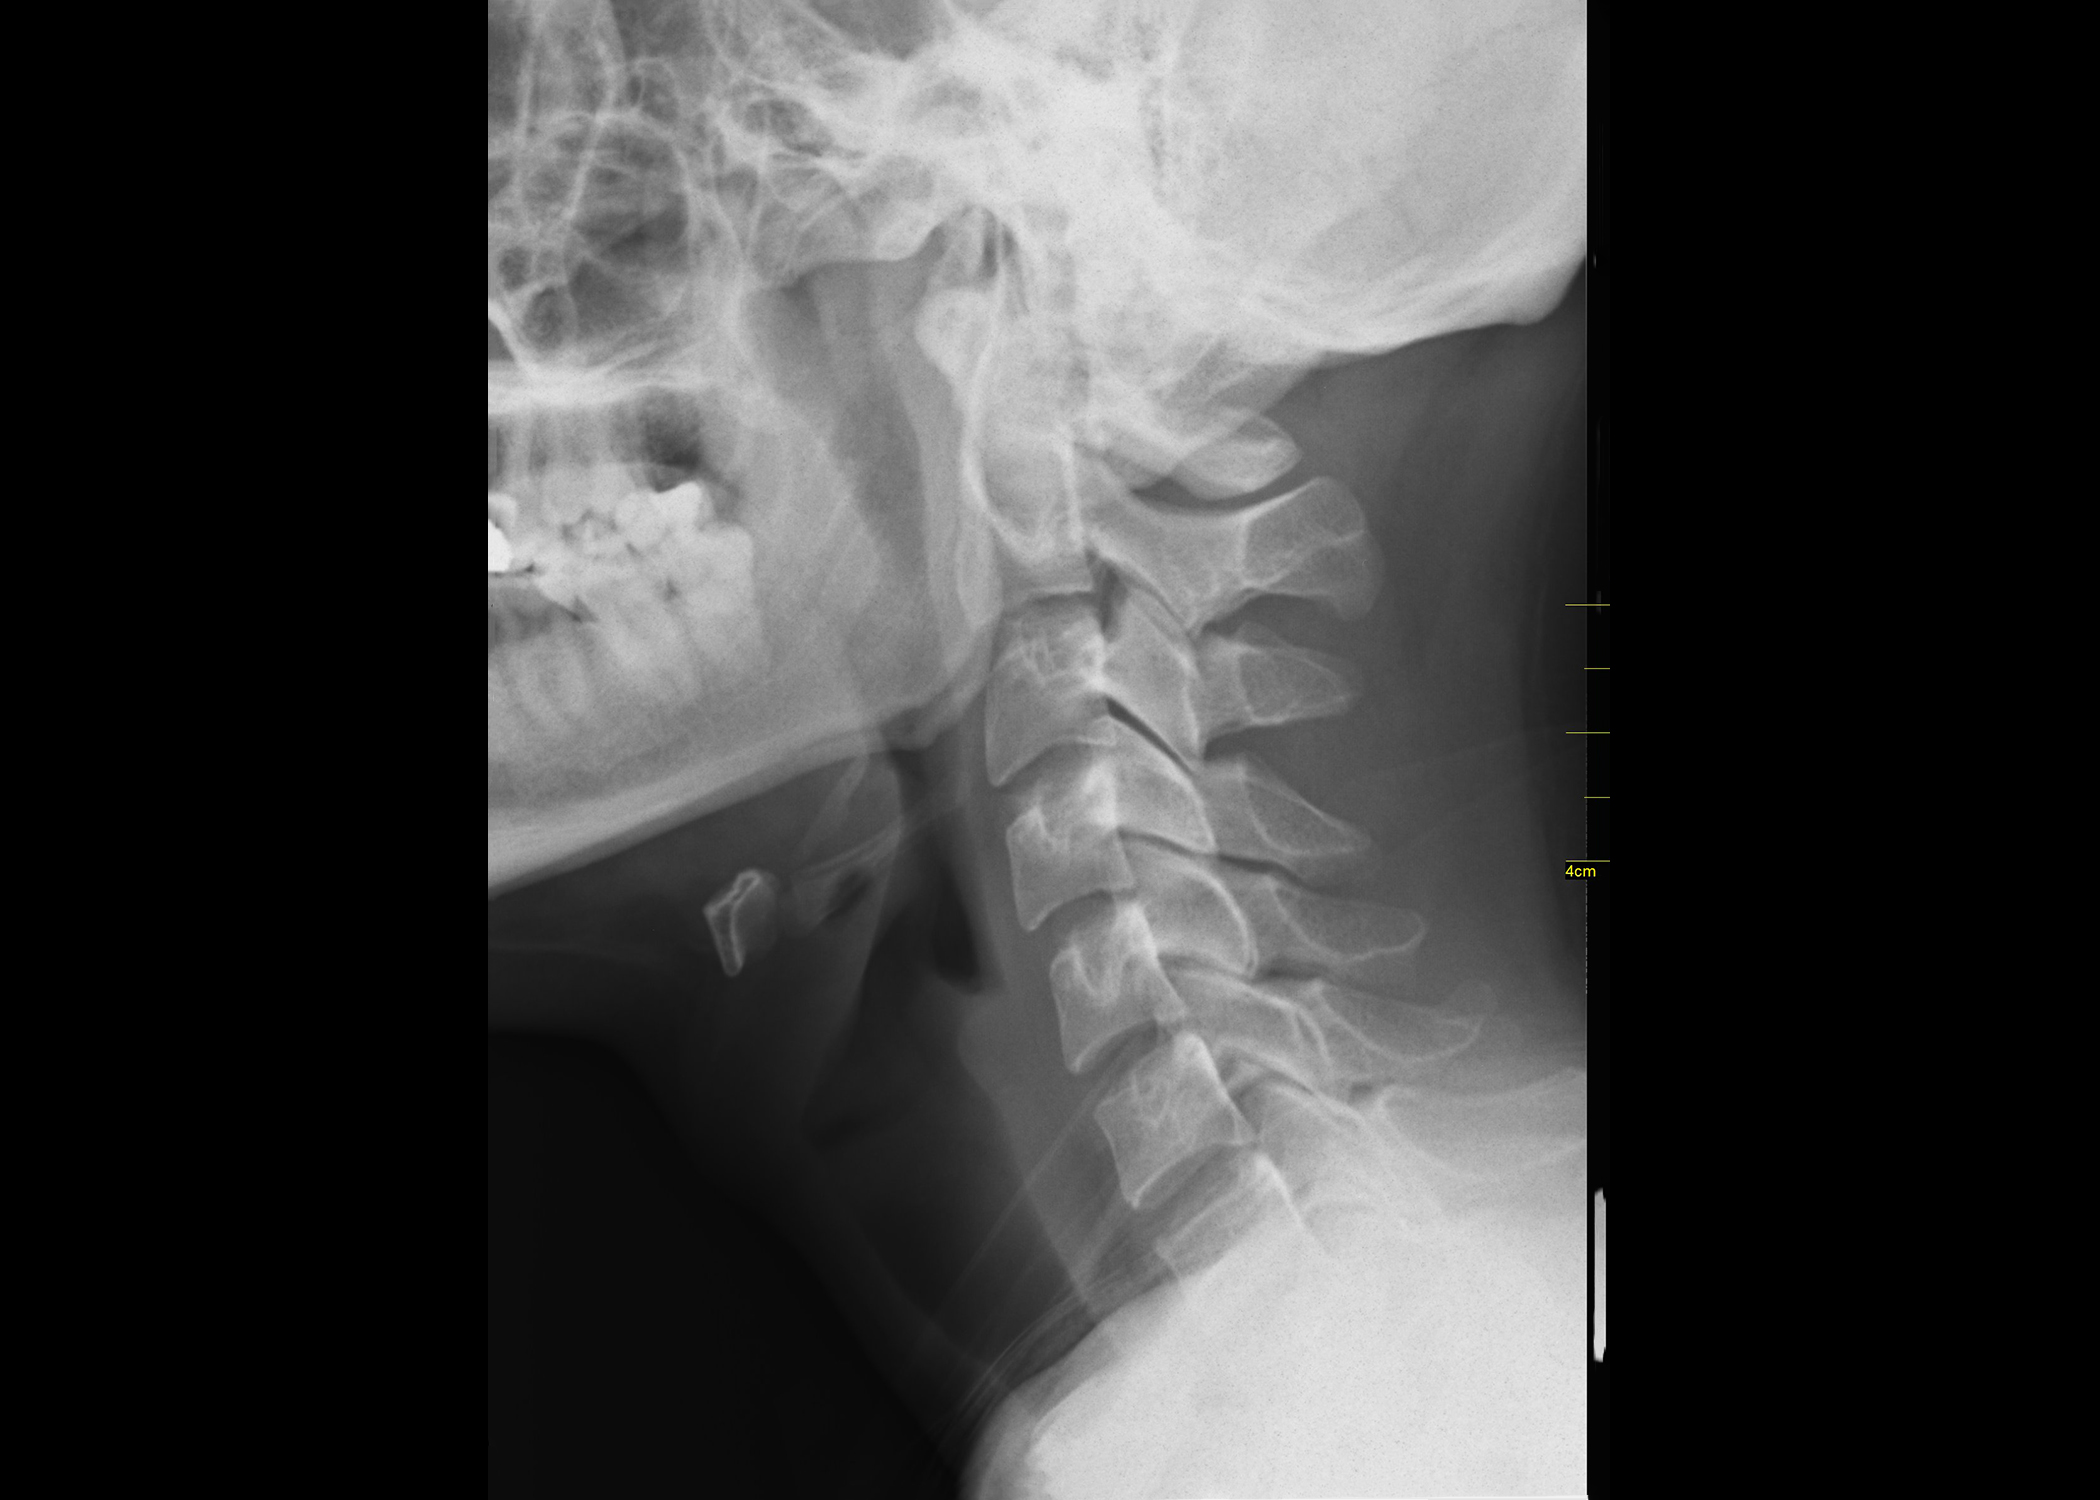

Top X-ray image by © Nevit Dilmen, CC BY-SA 3.0